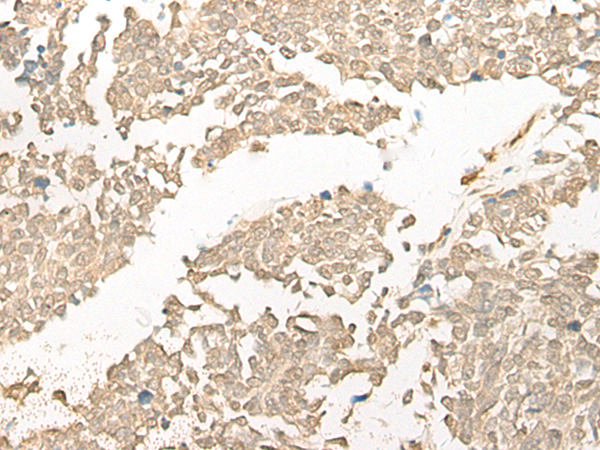

分类: 科研抗体货号: P09634别名: HEL-S-98n应用: WB,IHC反应种属: Human